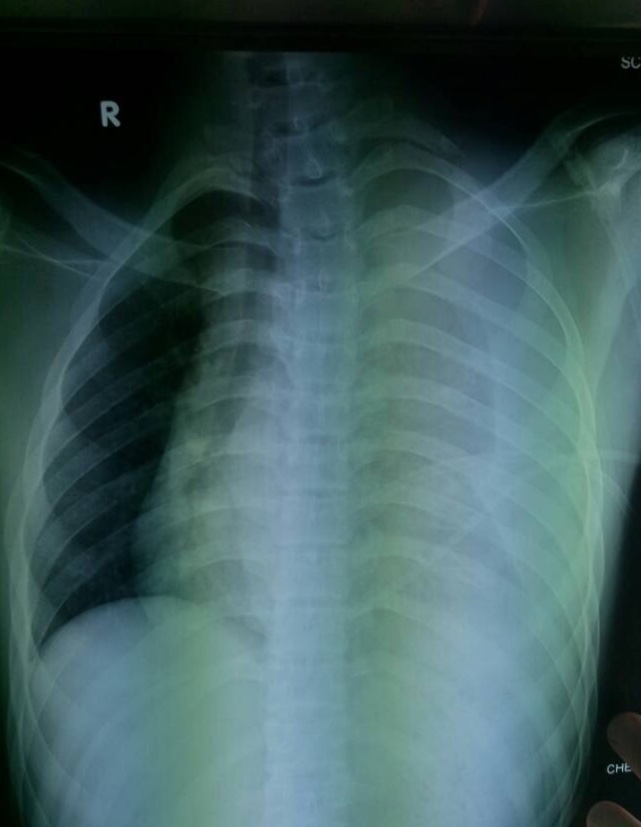

Figure 1. Image showing a massive left hemothorax, mediastinum displaced to the right with fracture of the first rib.

Resuscitation was initiated while a chest plain radiography on the bed was immediately performed (Figure 1). The author found the sign of a massive left hemothorax with mediastinal displacement to the right side, and the first left rib was fractured. The left clavicle remained intact. In this clinical setting, there was no time to make further imaging explorations, and the patient was urgently sent to the operating room for an emergency operation with a suspected diagnosis of fatal subclavian arterial rupture following blunt thoracic trauma.